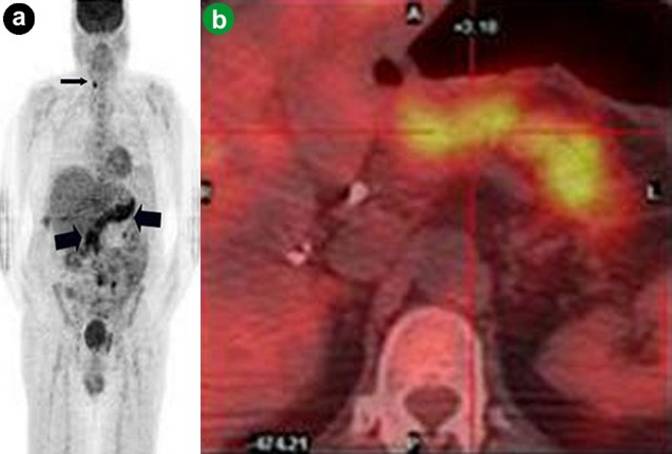

f) Pancreatic Metastasis from Melanoma

Melanoma is the sixth most common cancer in the United States. The incidence has tripled in the white population in the last 20 years. The most common metastatic sites are lungs, lymph nodes, gastrointestinal tract, brain, and bone (Figure 14). Pancreatic metastases occur in less than 5% of patients with distant metastatic sites (Figure 14). Current evidence supports using PET/CT in staging, restaging, and monitoring therapy for stage III and IV because of superior accuracy of PET/CT compared to CT alone in detecting distant metastases [13]. Early detection of metastases is crucial for patients with stage IV melanoma because, in selected cases, metastasectomy can improve the 5-year survival rate (20 months vs. 8 months).

|

Figure 14. a. Coronal PET maximum intensity projection image shows metastases of melanoma to the head of the pancreas (large arrow), right axilla, lower thoracic spine, right mesentery and left rib (small arrows). b. Coronal fused PET/CT image of another patient with melanoma metastasizing to the pancreas (arrow). |